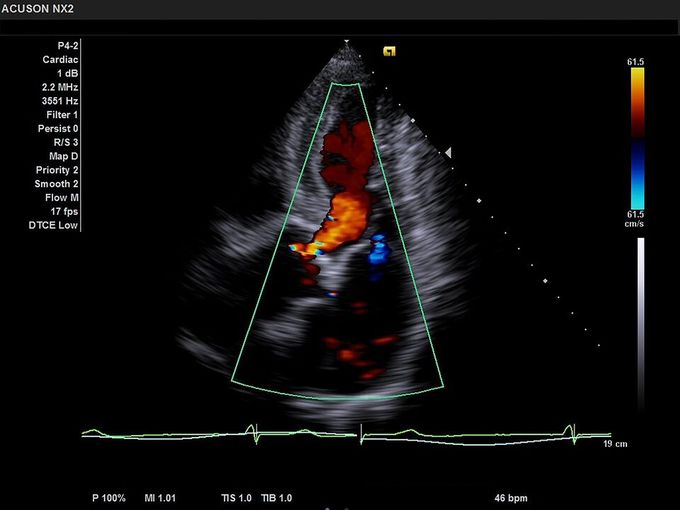

Кроме новой техники, можно заказать восстановленные медицинские системы: ультразвуковые сканеры, томографы, флюороскопы, ангиографы и хирургические установки С-дуга.